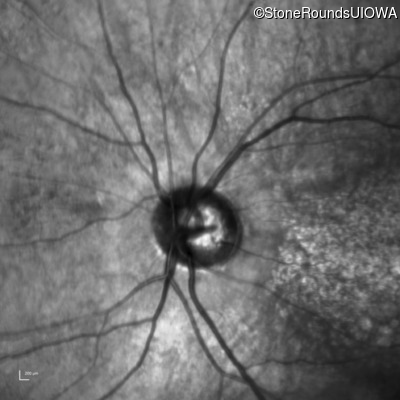

Infrared Fundus Photograph - Left - 10/160 -1

Exemplar